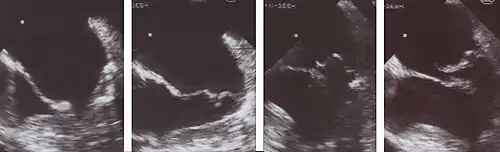

Mitralklappenprolaps (TEE-Aufnahmen)

Legende

1 Diastole: Beide Mitralsegel weit geöffnet

2 Frühe Systole: Beginnender Klappenschluss

3 Das posteriore Segel prolabiert in den linken Vorhof

4 Beginn der Klappenöffnung